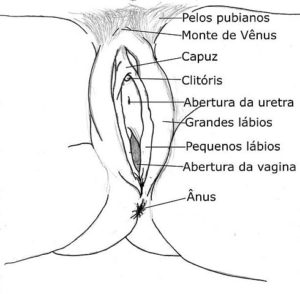

Vulva

Se conoce como vulva al conjunto de órganos genitales externos de la mujer. Está conformada por los labios mayores y menores, el clítoris y el monte del pubis o monte de Venus.

La anatomía vulvar difiere bastante de una persona a otra dependiendo de la contextura, tamaño, color de piel, grosor de los labios menores, entre otras características; por lo tanto, no es posible describir características anatómicas específicas que sean comunes para todas las mujeres.

La vulva está abundantemente irrigada por las tres arterias pudendas (pudenda externa superficial, pudenda interna y pudenda externa profunda).